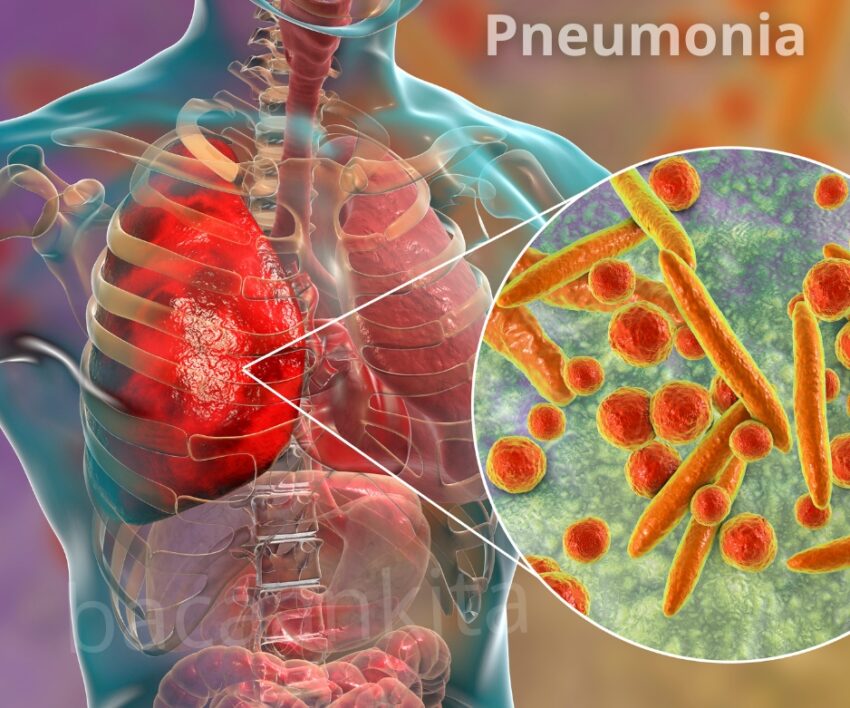

Pneumonia adalah penyakit infeksi yang bikin paru-paru lo kena dampaknya, biasanya disebabkan oleh bakteri, virus, atau jamur. Penyakit ini bikin kantong-kantong udara di paru-paru lo meradang dan bisa berisi cairan atau nanah, yang akhirnya bikin susah napas. Kalo nggak ditangani dengan baik, penyakit ini bisa berbahaya banget, apalagi buat anak kecil, lansia, atau orang dengan sistem imun yang lemah. Jadi, penting banget untuk kenali gejala dan tahu cara penanganannya.

Bakteri adalah penyebab penyakit ini yang paling umum. Salah satu bakteri yang sering terlibat adalah Streptococcus pneumoniae, yang sering muncul setelah seseorang terkena flu atau pilek. Selain itu, ada juga Mycoplasma pneumoniae, yang menyebabkan pneumonia ringan yang biasa disebut “walking pneumonia” karena penderitanya masih bisa beraktivitas meski dalam kondisi lemah.